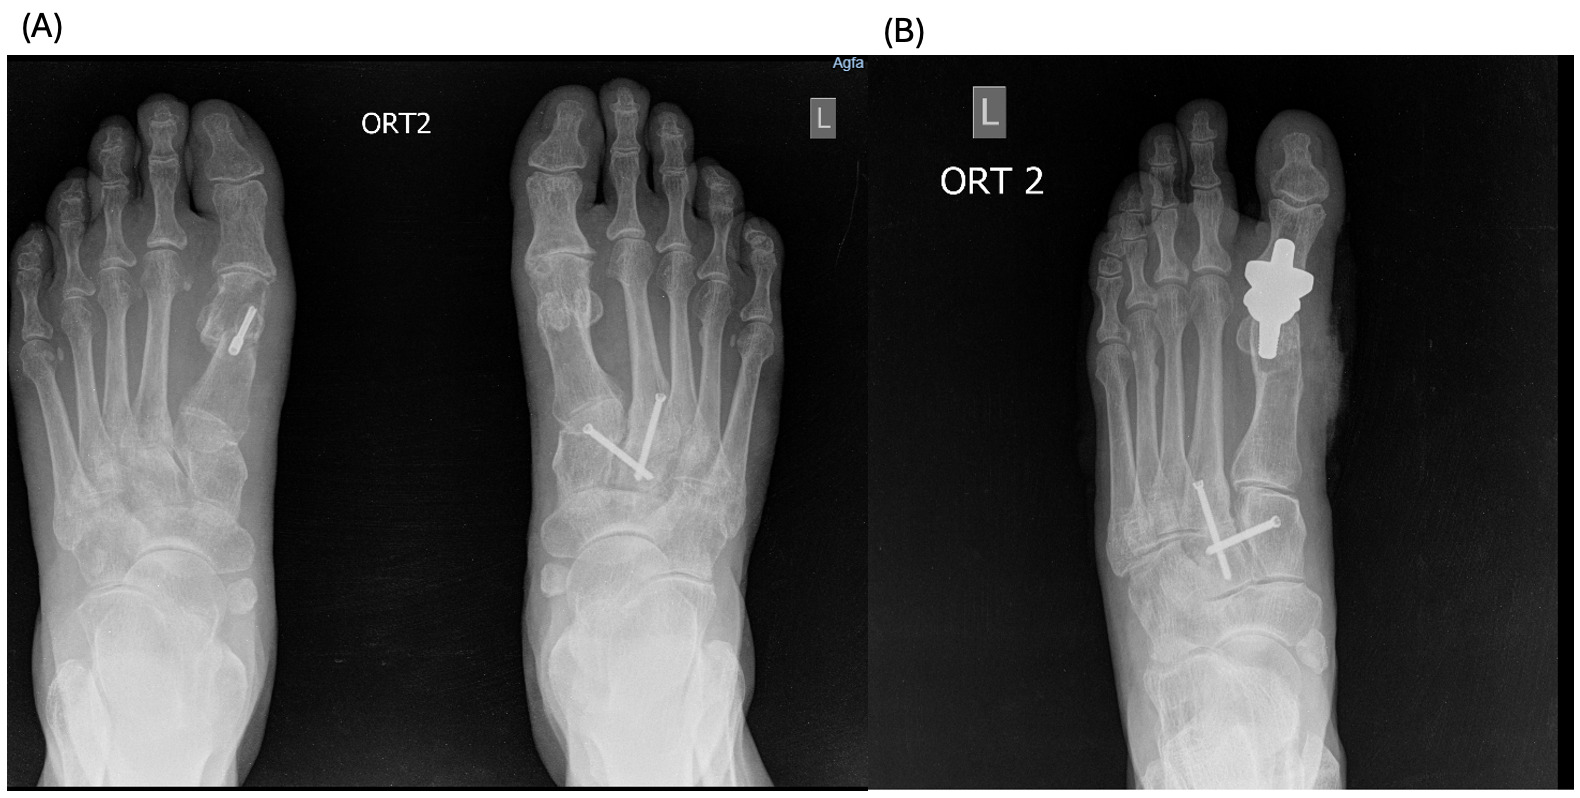

Case #3 (R.A.)

A 58-year-old female patient with a history of arthrodesis of left foot midfoot in 2021, and minimally invasive surgery of the right foot in 2024. The patient had complaints of decreased range of motion and pain on movement of the left foot for the last 5 years. Patient reports worsening after trauma (fall) 7 days ago, since when edema of the left foot appeared, and pain became constant with no response to painkillers. Physical examination revealed crepitus on movement of the first MTP joint and almost no movement (Figure 3 A).

2 and 6 months after the procedure, the patient reports no pain of any type of movement in the joint and improvement in the mobility of the first MTP (Figure 3 B).

The patients had undergone radiographic evaluation of the MTP joint before the surgery, right after surgery, and 2 and 6 months after surgery (Figures 4-9). The radiographic imaging after the surgery confirmed the correct positioning and alignment. At the follow-up, the radiographic images were done to analyze the early healing process, to observe if there were any signs of implant loosening. 2 months after the surgery, no patient had periprosthetic radiolucencies, no stress-related changes. 6 months after surgery, no osteolysis, no migration of the implant.

This case series demonstrates successful short-term results following total first metatarsophalangeal (MTP) joint replacement using ceramic implants in patients with hallux rigidus. All three patients presented significant improvement in AOFAS scores within 2 months postoperatively, with preserved improvement at 6 months. Notably, Patient C, who had the lowest preoperative score (27/100), achieved the greatest relative improvement, reaching 92/100 at 2 months and 89/100 at 6 months. These functional outcomes were confirmed by physical examination findings, with clear improvements in joint alignment and reduction in deformity (Figure 1-3, (B, C)). Moreover, radiographic imaging revealed no signs of complications such as implant loosening, migration or stress-related changes.